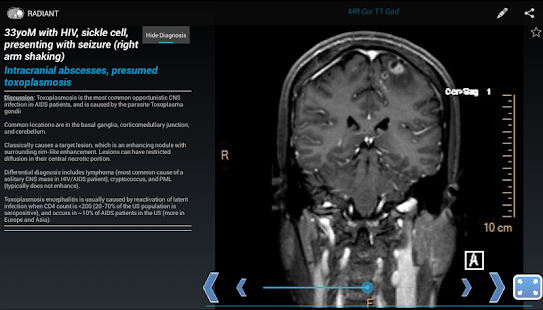

RADIANT: Share Radiology Cases Screen Preview

RADIANT is a platform to create, manage, and share image-based educational materials, primarily intended for users in the medical field. It is ideal for sharing interesting cases among diagnostic radiology residents, fellows, medical students, and faculty. It is NOT meant to be used for diagnosis.

Content is organized around a single image as the fundamental component. Multiple related images comprise a series, which allows for scrolling through the image stack. These image series form the building blocks for Cases (related series demonstrating the imaging findings for a specific diagnosis in one particular patient), Teaching Files (topics organized in chapters and sub-chapters like a text book), and Tests (linked questions with associated image series). Cases can be grouped together in to Case Packs, which take only seconds to create, and are perfect for last minute unknown case presentations and focused studying.

With RADIANT, you can create cases showing x-rays, ultrasound, CT, MRI, or any other imaging modality. It is a great way to learn chest x-rays, normal anatomy, and common disease processes, using real, high-quality diagnostic medical images.